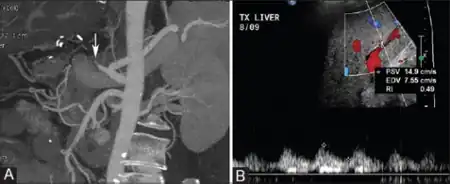

Hepatic artery thrombosis may cause severe elevations in serum aminotransferases, alanine transaminase (ALT) and aspartate transaminase (AST).[4] Often the AST is greater than the ALT.[4] Hepatic artery thrombosis is usually diagnosed with ultrasound with doppler, although it may be diagnosed using computed tomography (CT) or magnetic resonance imaging (MRI).

Hepatic artery thrombosis is diagnosed with ultrasound with doppler, which shows a lack of blood flow through the hepatic artery.[2] Hepatic artery thrombosis may also be diagnosed using CT or MR imaging, which would show evidence of a blood clot within the hepatic artery.[2]